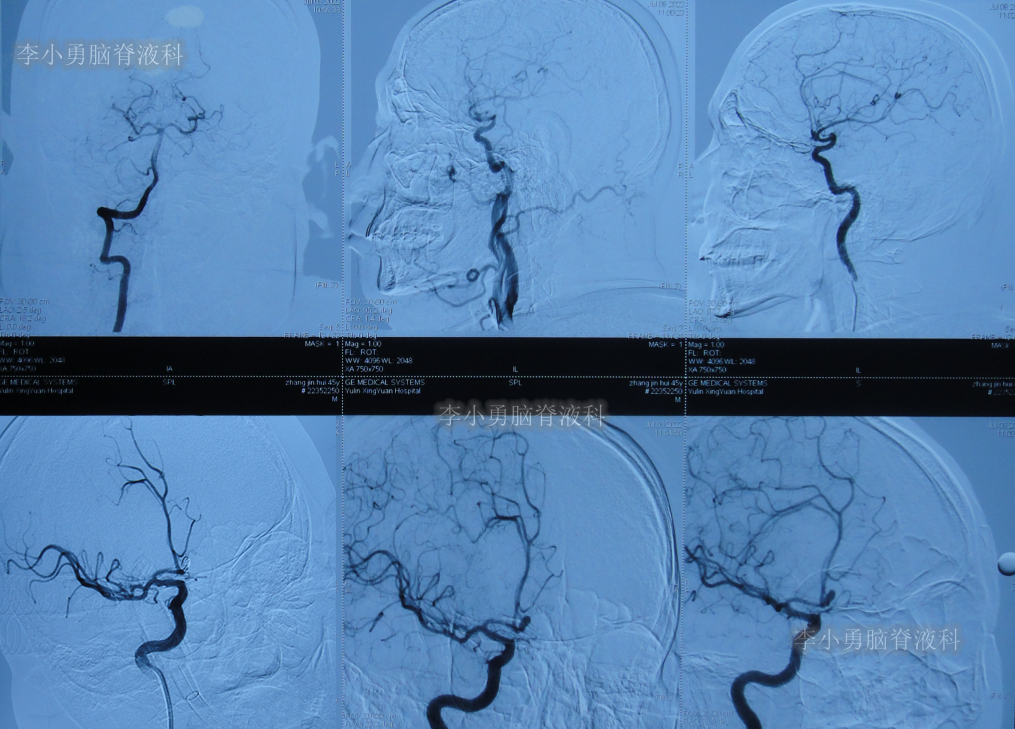

患者于2022年7月8日凌晨突发头痛,伴有胡言乱语,右下肢明显乏力,被家属送至附近的陕西省榆林市某医院,查头颅CT示脑出血(图-1),考虑脑动脉瘤破裂;当即给予了DSA检查发现前交通动脉瘤(图-2)。

图-2:2022年7月8日头颅DSA